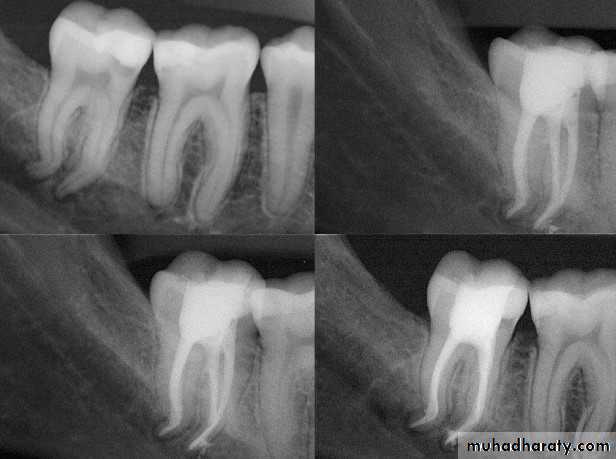

2- Gutta percha carrier devices: (Thermafil)

These are cores of metal or plastic coated with gutta percha. They are heated in an oven and then simply pushed into the root canal to the correct length. The core is then cut with a bur. A dense filling results, but apical control is poor and extrusions common. They are expensive and difficult to remove.Advances in gutta percha

A

B

C

D